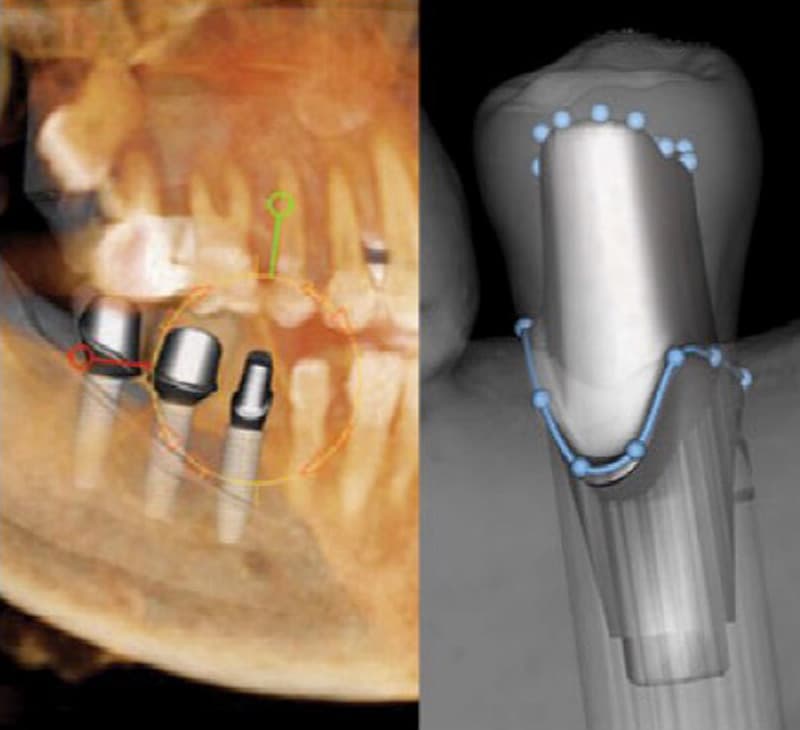

Ever-evolving Tools for More Complete Implant Planning

By Justin Moody, DDS, DICOI, DABOI Much has been written about cone beam 3D imaging and its benefits to the placement of dental implants. The amount of data that can be gained from 3D scans has become an integral part of my diagnosing patients’ individual needs. Data and measurements for dental applications such as bone height, buccolingual dimensions, and angulation help me to define the best positioning, and scans also show detailed views of the maxillary sinus, inferior alveolar nerve, and nasal cavity, among other anatomical landmarks. While the 3D view offers this precise look at the anatomy, often the treatment planning software is the star of the show.